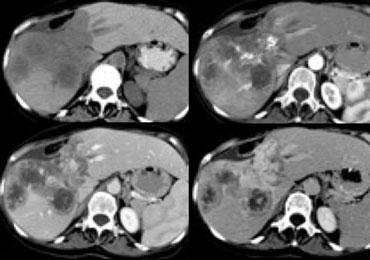

NECT, arterial and portal venous phase in a patient with Hepatitis C with two lesions in the liver (arrows).

Trong thì động mạch, chúng ta thấy hai tổn thương tăng sinh mạch.

Các hình ảnh phía trên cho thấy một tổn thương đồng tỷ trọng với gan trên CCLVT không tiêm thuốc.

Trong thì động mạch có sự ngấm thuốc, nhưng không đậm bằng tỷ trọng máu trong lòng mạch.

Trong thì tĩnh mạch cửa, tổn thương lại đồng tỷ trọng với nhu mô gan xung quanh và không thể nhìn thấy.

Nếu chỉ có thì tĩnh mạch cửa, chắc chắn bạn sẽ bỏ sót tổn thương này.

Các hình ảnh phía dưới cho thấy một tổn thương có thể nhìn thấy trên tất cả các hình ảnh.

Bạn thấy nó trên CCLVT không tiêm thuốc và có thể nhận xét rằng nó giảm tỷ trọng so với gan.

Tuy nhiên, nếu nhìn vào tỷ trọng máu trong lòng mạch, bạn sẽ nhận thấy rằng ở tất cả các thì, tổn thương có tỷ trọng tương đương với máu trong lòng mạch.

Vậy chúng ta có một ung thư biểu mô tế bào gan ở thùy phải trên các hình ảnh phía trên và một u máu ở thùy trái trên các hình ảnh phía dưới.

Điều quan trọng là phải xem xét tất cả các thì chụp.